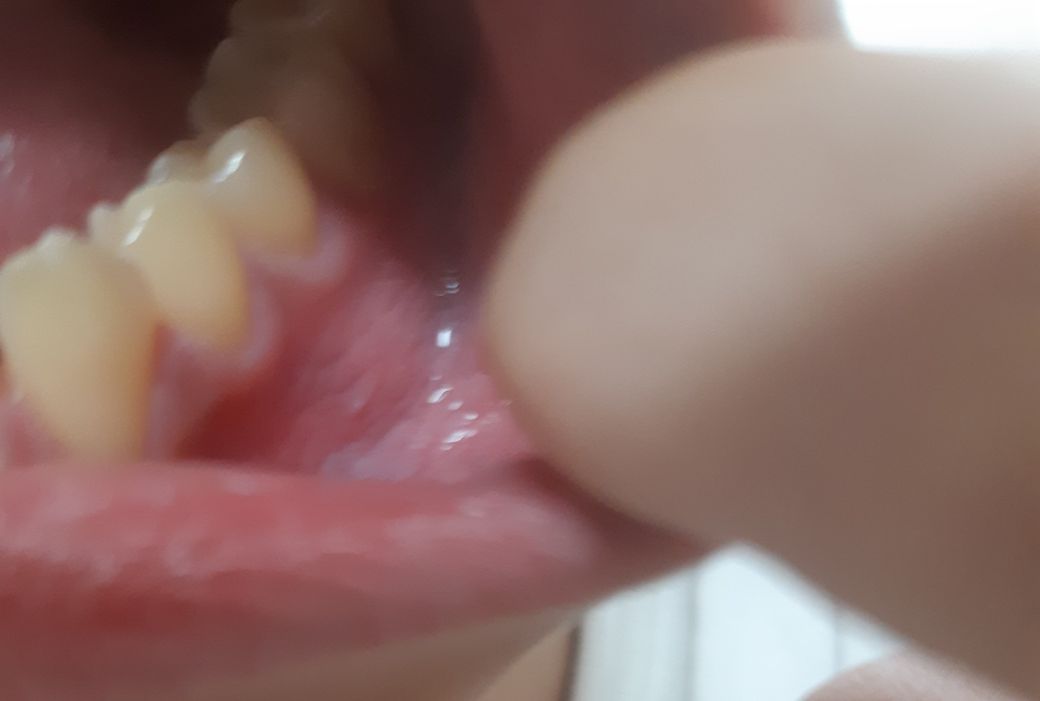

오른쪽 하악

왼쪽하악

입안 잇몸밑에 하악쪽 뼈있는곳이 자까 벗겨지고 까지집니다. 2년넘게 증상이 나아지지 않고 혀로 문질러 보면 느낌도 까칠하고 무슨 지렁이 같은게 붙어 있는거마냥 그런 느낌이 납니다 손가락으로 긁어서 보면 지우개 가루같이 흰색으로 되어있는 이물질들이 나옵니다. 치과에 가보니 충치 치주질환 등 그런것들은 아니라고 (인천에 있는 대학병원)큰병원에 가보라고 해서 혹시나 악성이 아닐까 걱정도 하고 ct도 찍어보았으나 아무런 문제가 없다고 하는데... 증상은 계속돼고... 이유가 뭘까요? 참고로 제가 후두염 식도염 있고 그리고 위가 좀 안좋은것같은데 연관성이 있을까요?